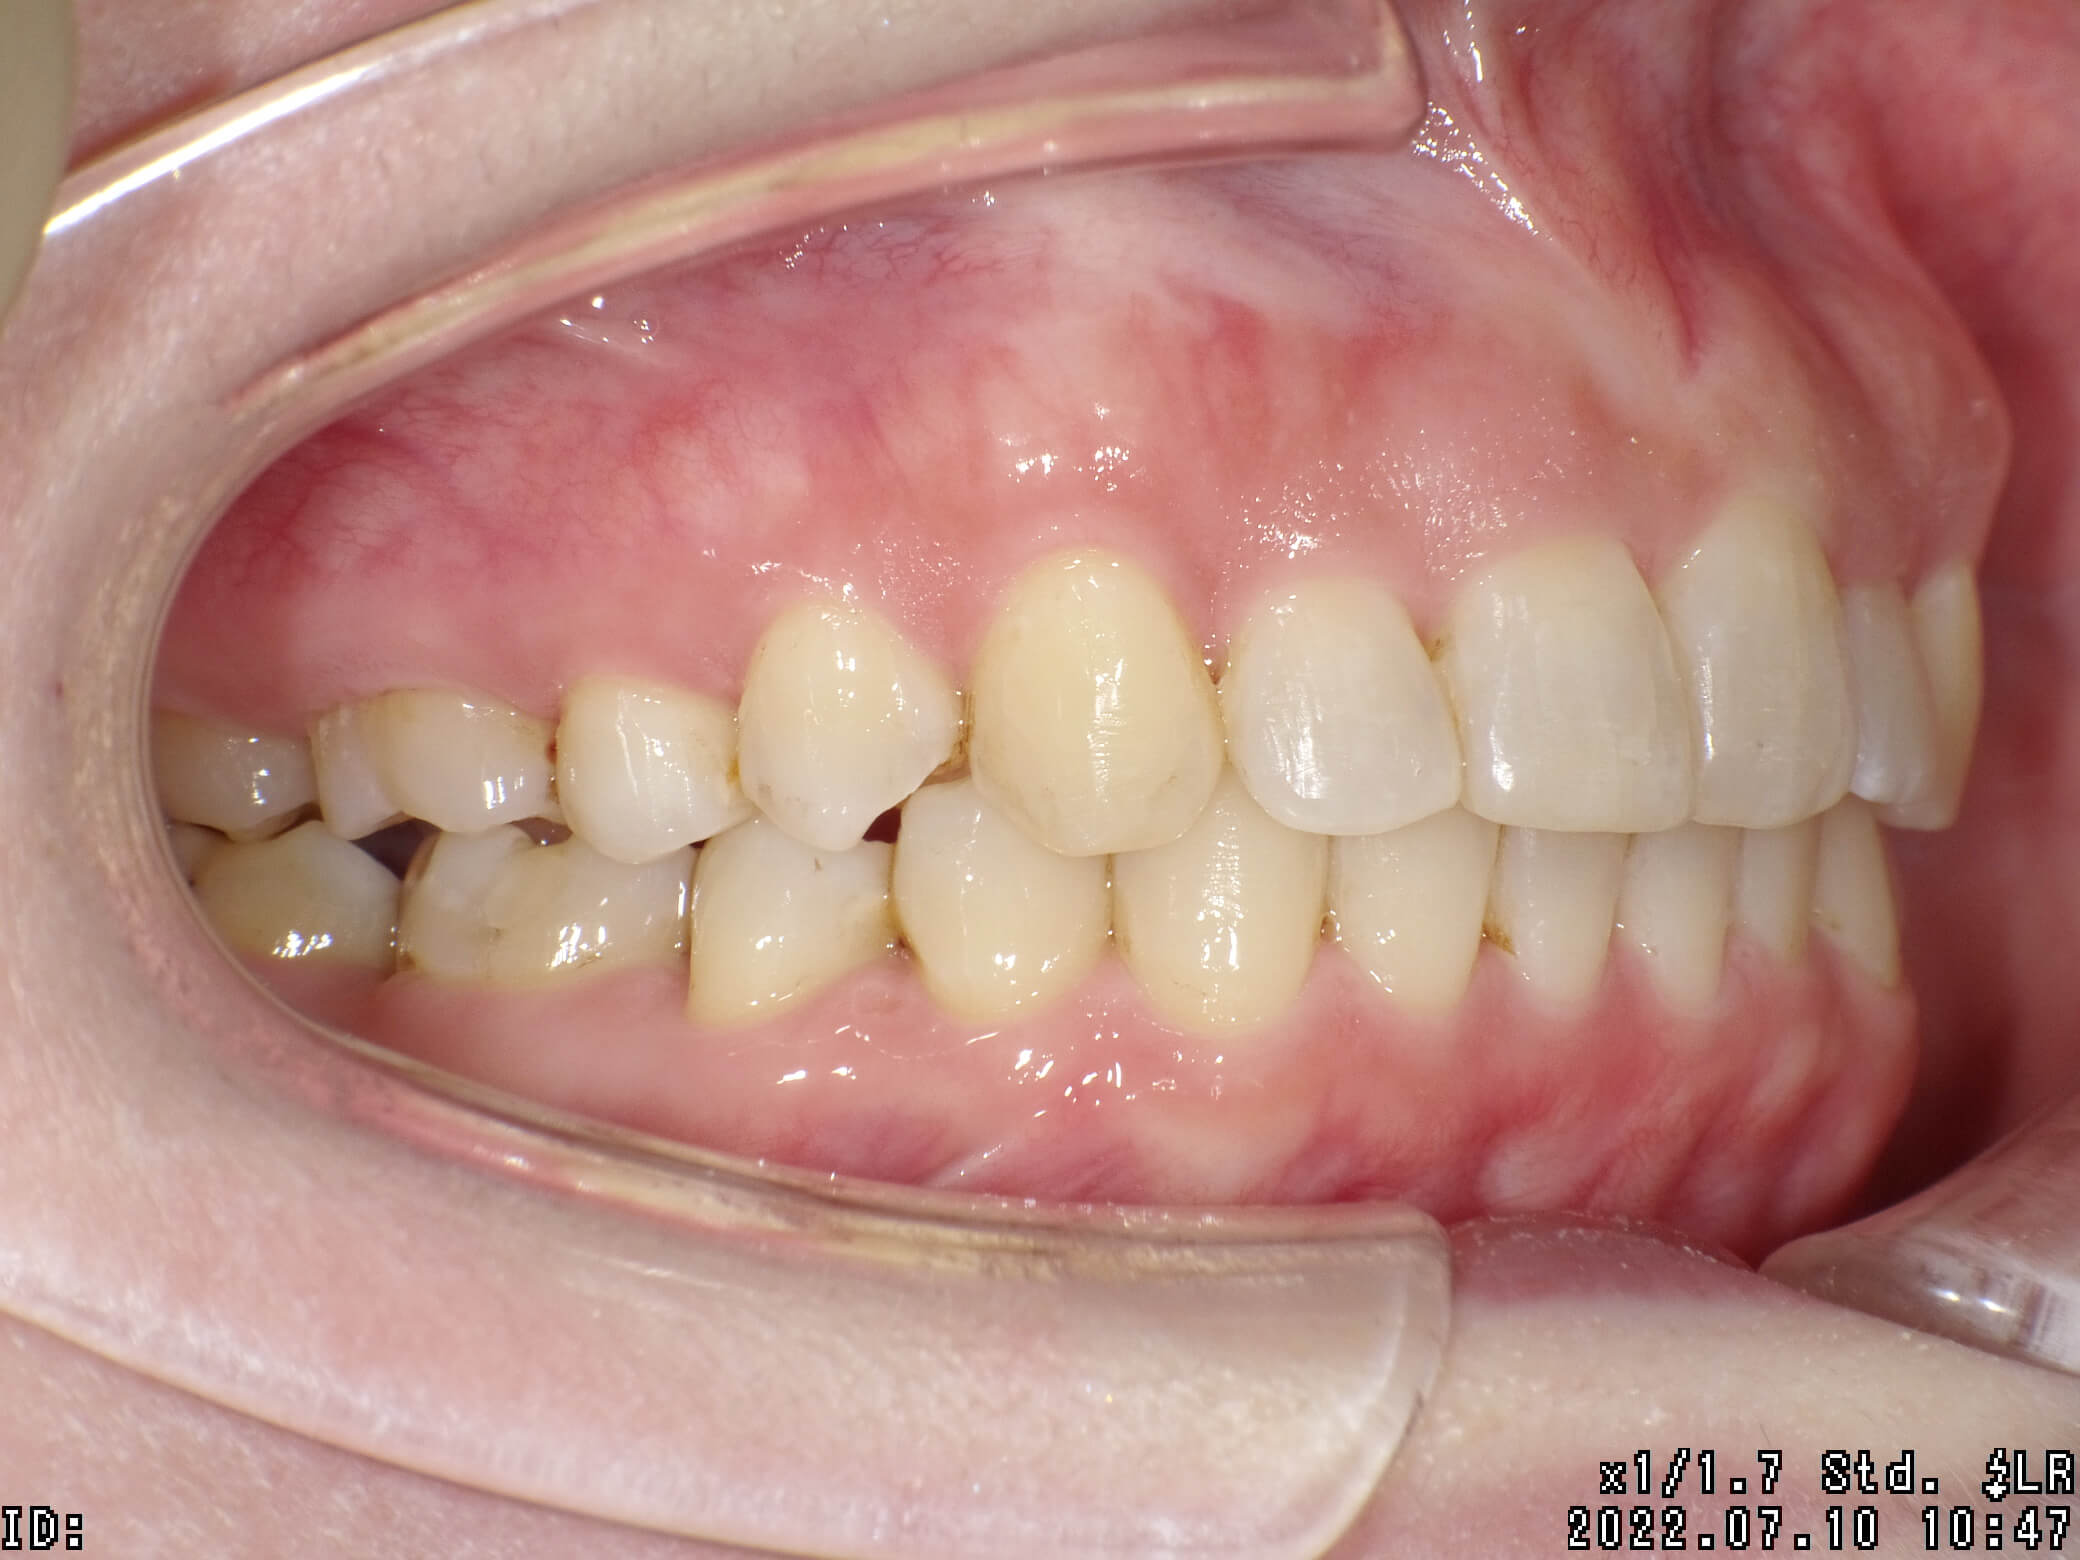

| 治療期間 | 2020年10月18日 〜2022年7月10日 |

|---|---|

| 治療費用 | 約770,000円 |

| 抜歯有無 | 抜歯なし |

| 矯正箇所 | クリアブラケット矯正 |